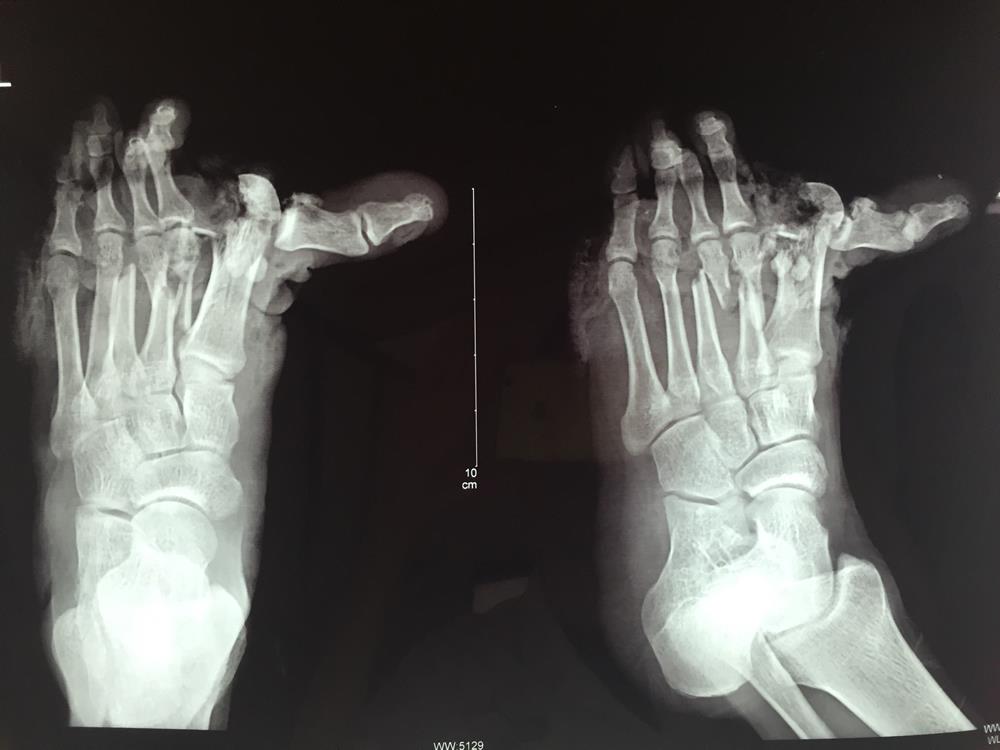

博爱医院手足一科王正理主治医师接诊时,患者的左足5个足趾苍白,血供消失,足背伸肌支持带至跖趾横纹处皮肤剥脱缺损,残留皮肤挫伤严重,创口污染严重……加之足趾离断,再植成活率极低,手术难度极高。

面对如此严重的伤情和手术难度,在手足一科主任吴春的指导下,王正理医师以最快的时间拟定了方案,通过改良足趾再植体位,争分夺秒地进行手术,手术经过5个多小时,在显微镜下吻合10多条血管以及5个足趾肌腱、神经,并采用负压封闭引流装置覆盖足背创面,手术取得成功,5个足趾血供得到恢复。在经过了后续的创面修复、内固定拆除及整形术,吴某逐渐恢复正常行走功能,回到了工作岗位。